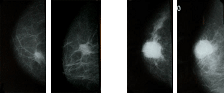

유방의 양 옆면과 상하를 누른 후 촬영하여 영상을 얻는 방법으로 유방조직내의 석회화병변이나 멍울을 확인할 수 있는 검사 방법 우리나라 여성의 경우 폐경전에는 유방 조직 밀도가 높아 종괴를 식별하기 어려운 경우가 종종 있으므로 유방촬영과 함께 초음파 검사를 실시하면 보다 정확 한 검사결과를 얻을 수 있습니다.